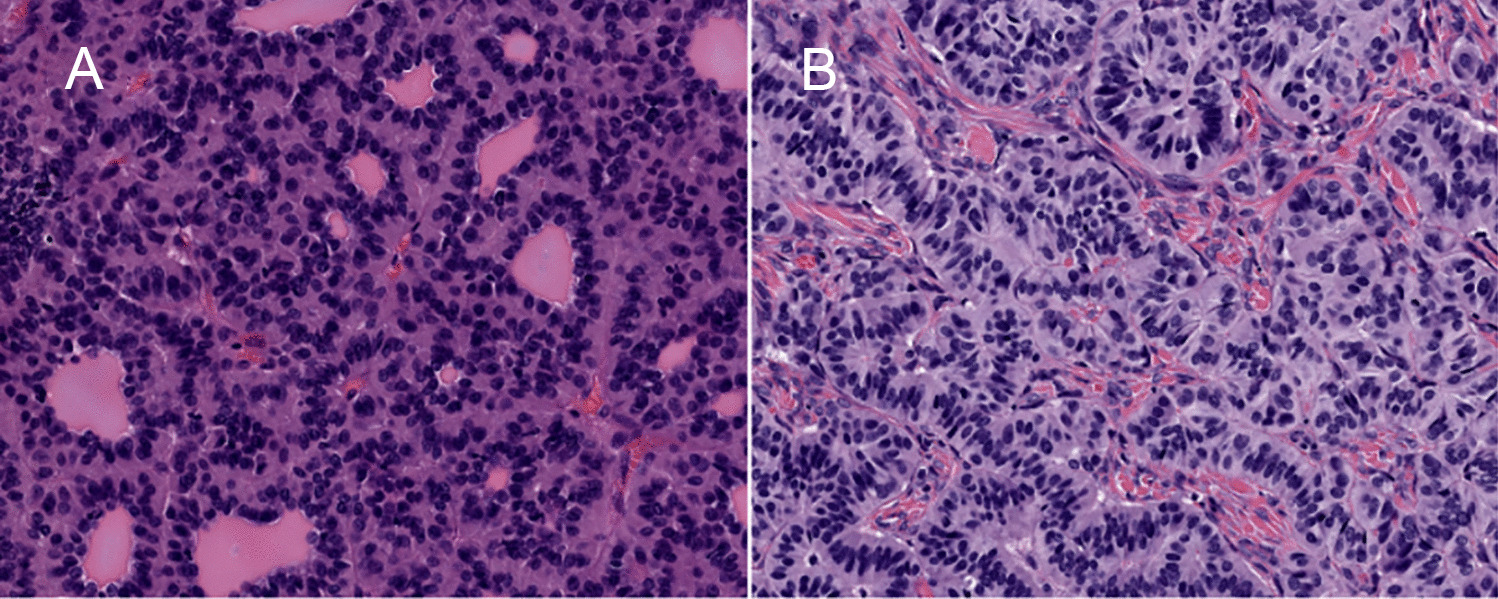

Histopathology revealed three distinct tumor components (Fig. 1C). The first component was characterized by scant infiltra...

Cauda Equina Neuroendocrine Tumors with Ganglioneuromatous Elements are Best Classified as Composite Gangliocytoma/Neuroma and Neuroendocrine Tumor (COGNET)

Rapid Evolution of Metastases in Patients with Treated G3 Neuroendocrine Tumors Associated with NEC-Like Transformation and TP53 Mutation

Little is known about the morphomolecular features of G3 neuroendocrine tumors (G3NETs) under prolonged systemic treatment...